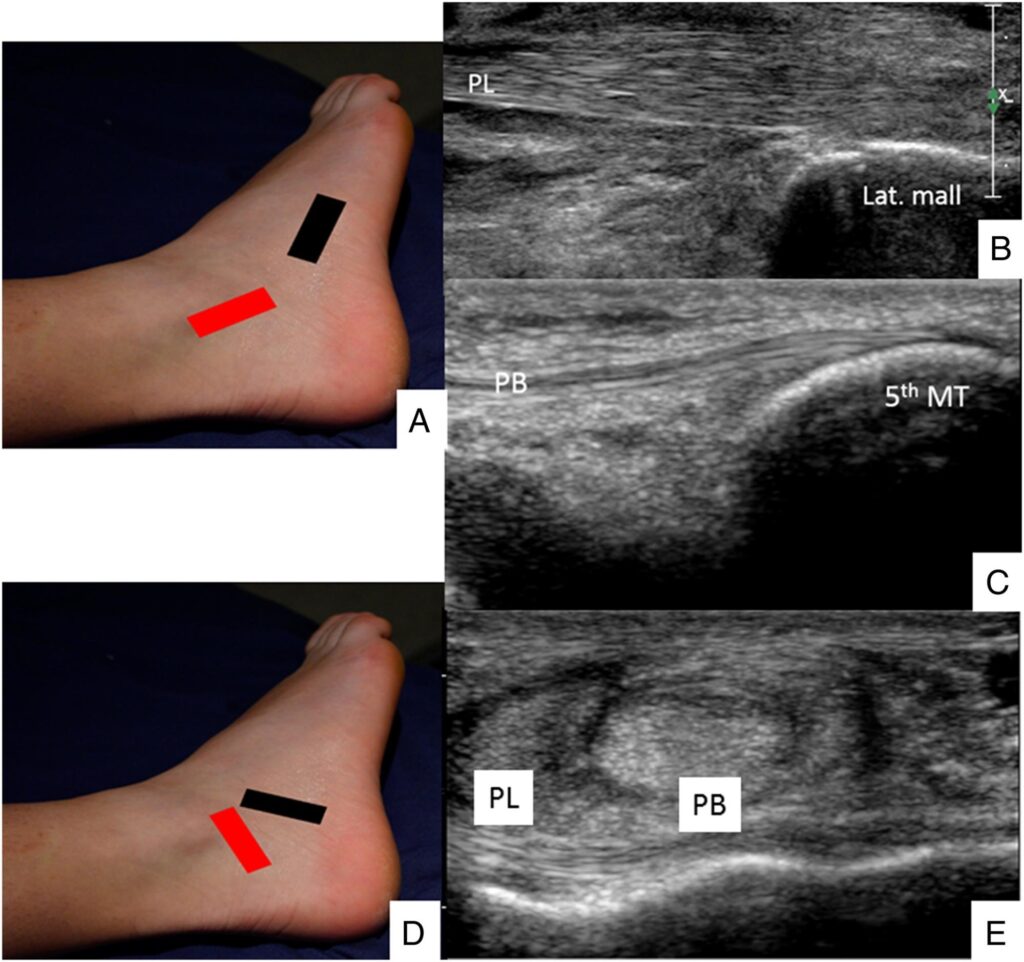

It’s a live, dynamic assessment of your muscles, tendons, ligaments, and soft tissues.

• Ankle

• Ligament sprains

• Tendon injuries

• Chronic instability

• Swelling or fluid